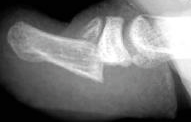

What is this called and how do you treat it?

Seymour fracture- juxtaepiphyseal fracture of the distal phalanx

Treatment of a nail bed avulsion and physeal separation is irrigation and debridement, physeal reduction, nail bed repair and immobilization. The primary goals are to achieve a stable, viable nail and good cosmetic results.